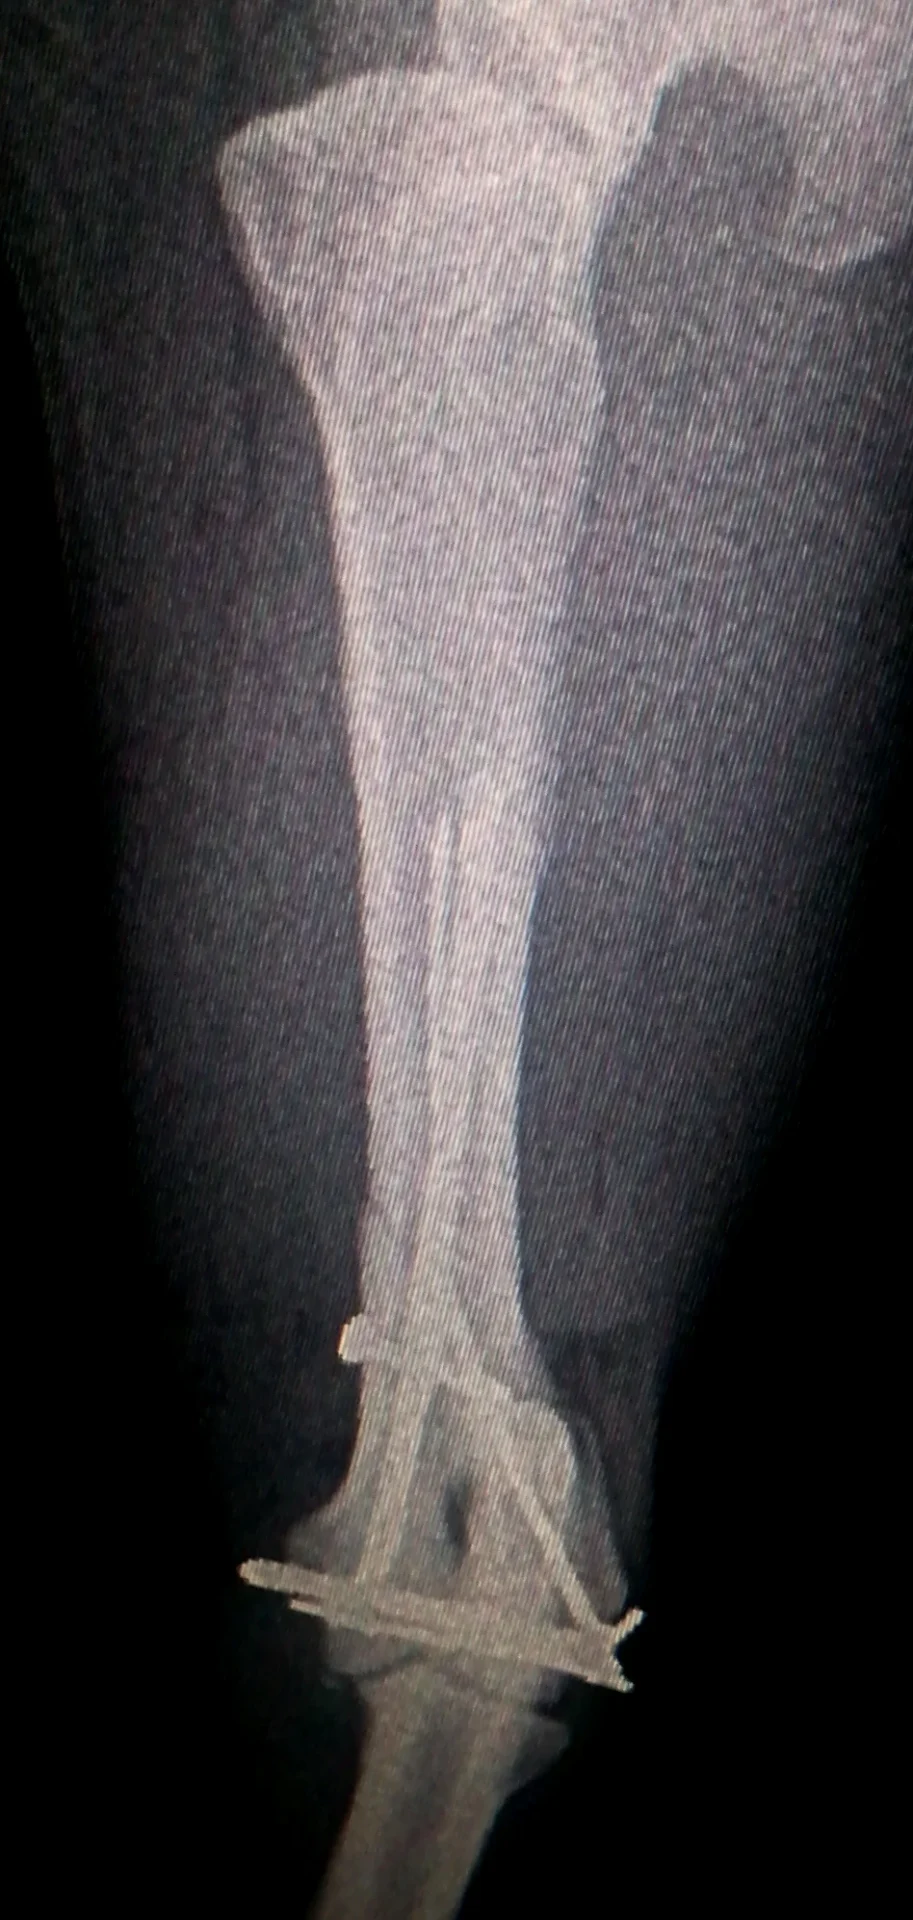

Galería de casos clínicos

Casos clínicos de cirugía (tejidos blandos, traumatología, neurocirugía, artroscopia)